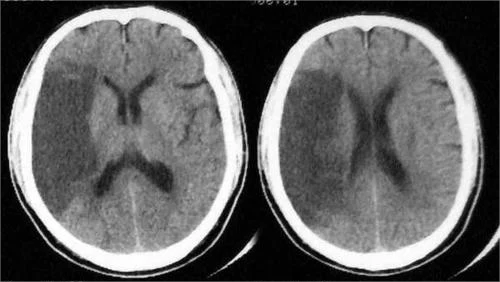

影像学检查,如CT和MRI,是确诊腔隙性脑梗死的金标准。CT可以显示脑组织中的低密度病灶,而MRI则能够更清楚地展示小血管的闭塞情况及其引起的细微病变。